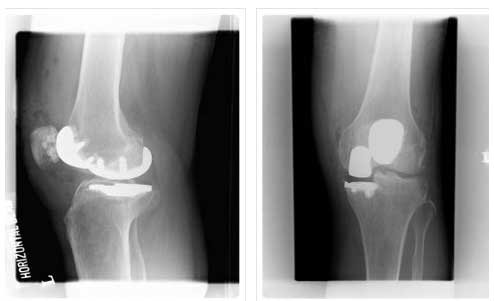

BILATERAL PATELLOFEMORAL REPLACEMENT

BILATERAL PATELLOFEMORAL REPLACEMENT

LATERAL VIEW